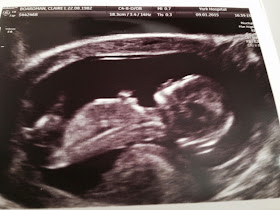

First appointment with our obstetrician today, without expecting it she pulled a few strings and ushered us into a little room and we got to see this..

It was overwhelming to see that little heartbeat flickering away, like a tiny butterfly flapping its wings saying 'look at me' i'm alive. I can't describe the relief, it's overwhelming. We are so lucky that we had this advantage, I don't know how people cope waiting for the 12 weeks. Wow, Just wow. So beautiful I shed a little tear.

So everything was fine with our little poppet yesterday.. here she is! (I say she, Mark says he).

She was fast asleep on her tummy and facing away from us so we had to give her a jiggle, we were rewarded with a full on somersault and wave, thumb sucking and disco dancing. It took ages to get some good pictures as the little monkey wouldn't keep still and kept turning away. She seems happy and is measuring a week more than my dates, and my dates are very precise so that can only mean one thing, she's ahead and she's strong! And she'll need all her strength, because I'm not so great. My BP is all over place, and I'm off work for a few more days til we can get it settled. I'm going to see my high risk OBGYN Tuesday but I'm going to try and ring renal to see if someone can check me over sooner, some pretty scary readings last night and this morning.